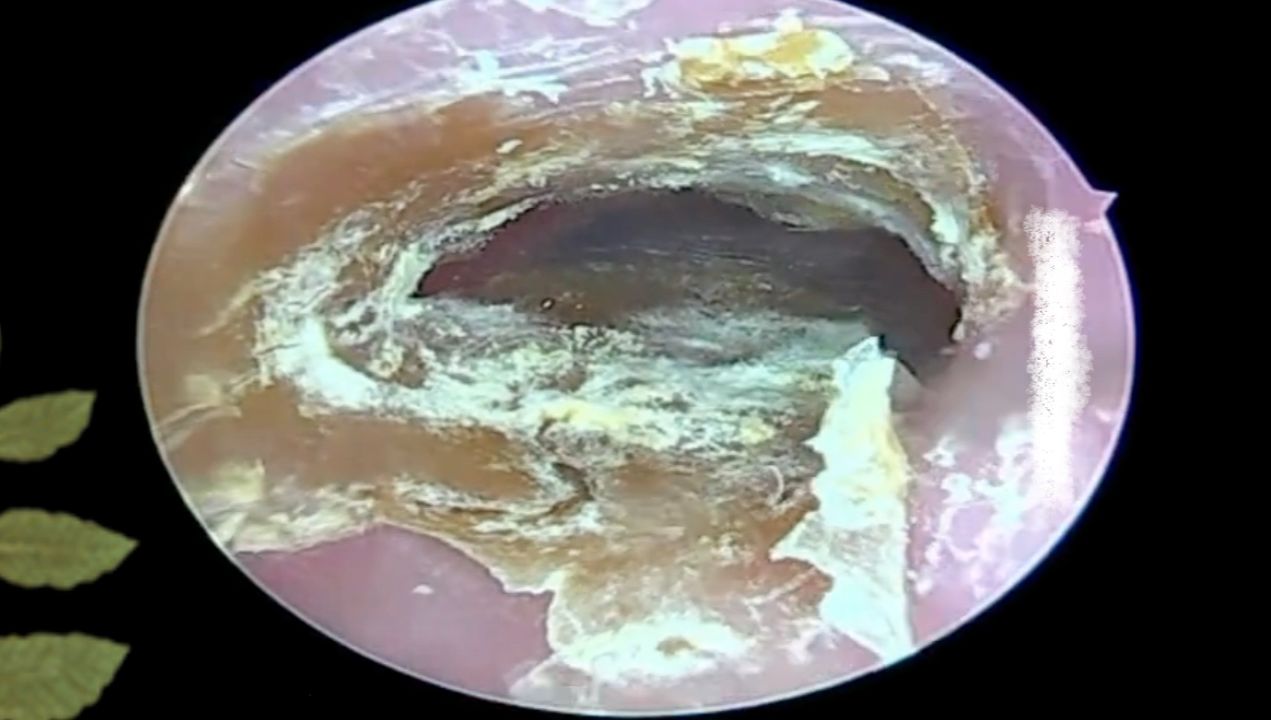

耳朵里好大一块霉菌干片,撕开发现耳道都化脓了

图片尺寸1689x950